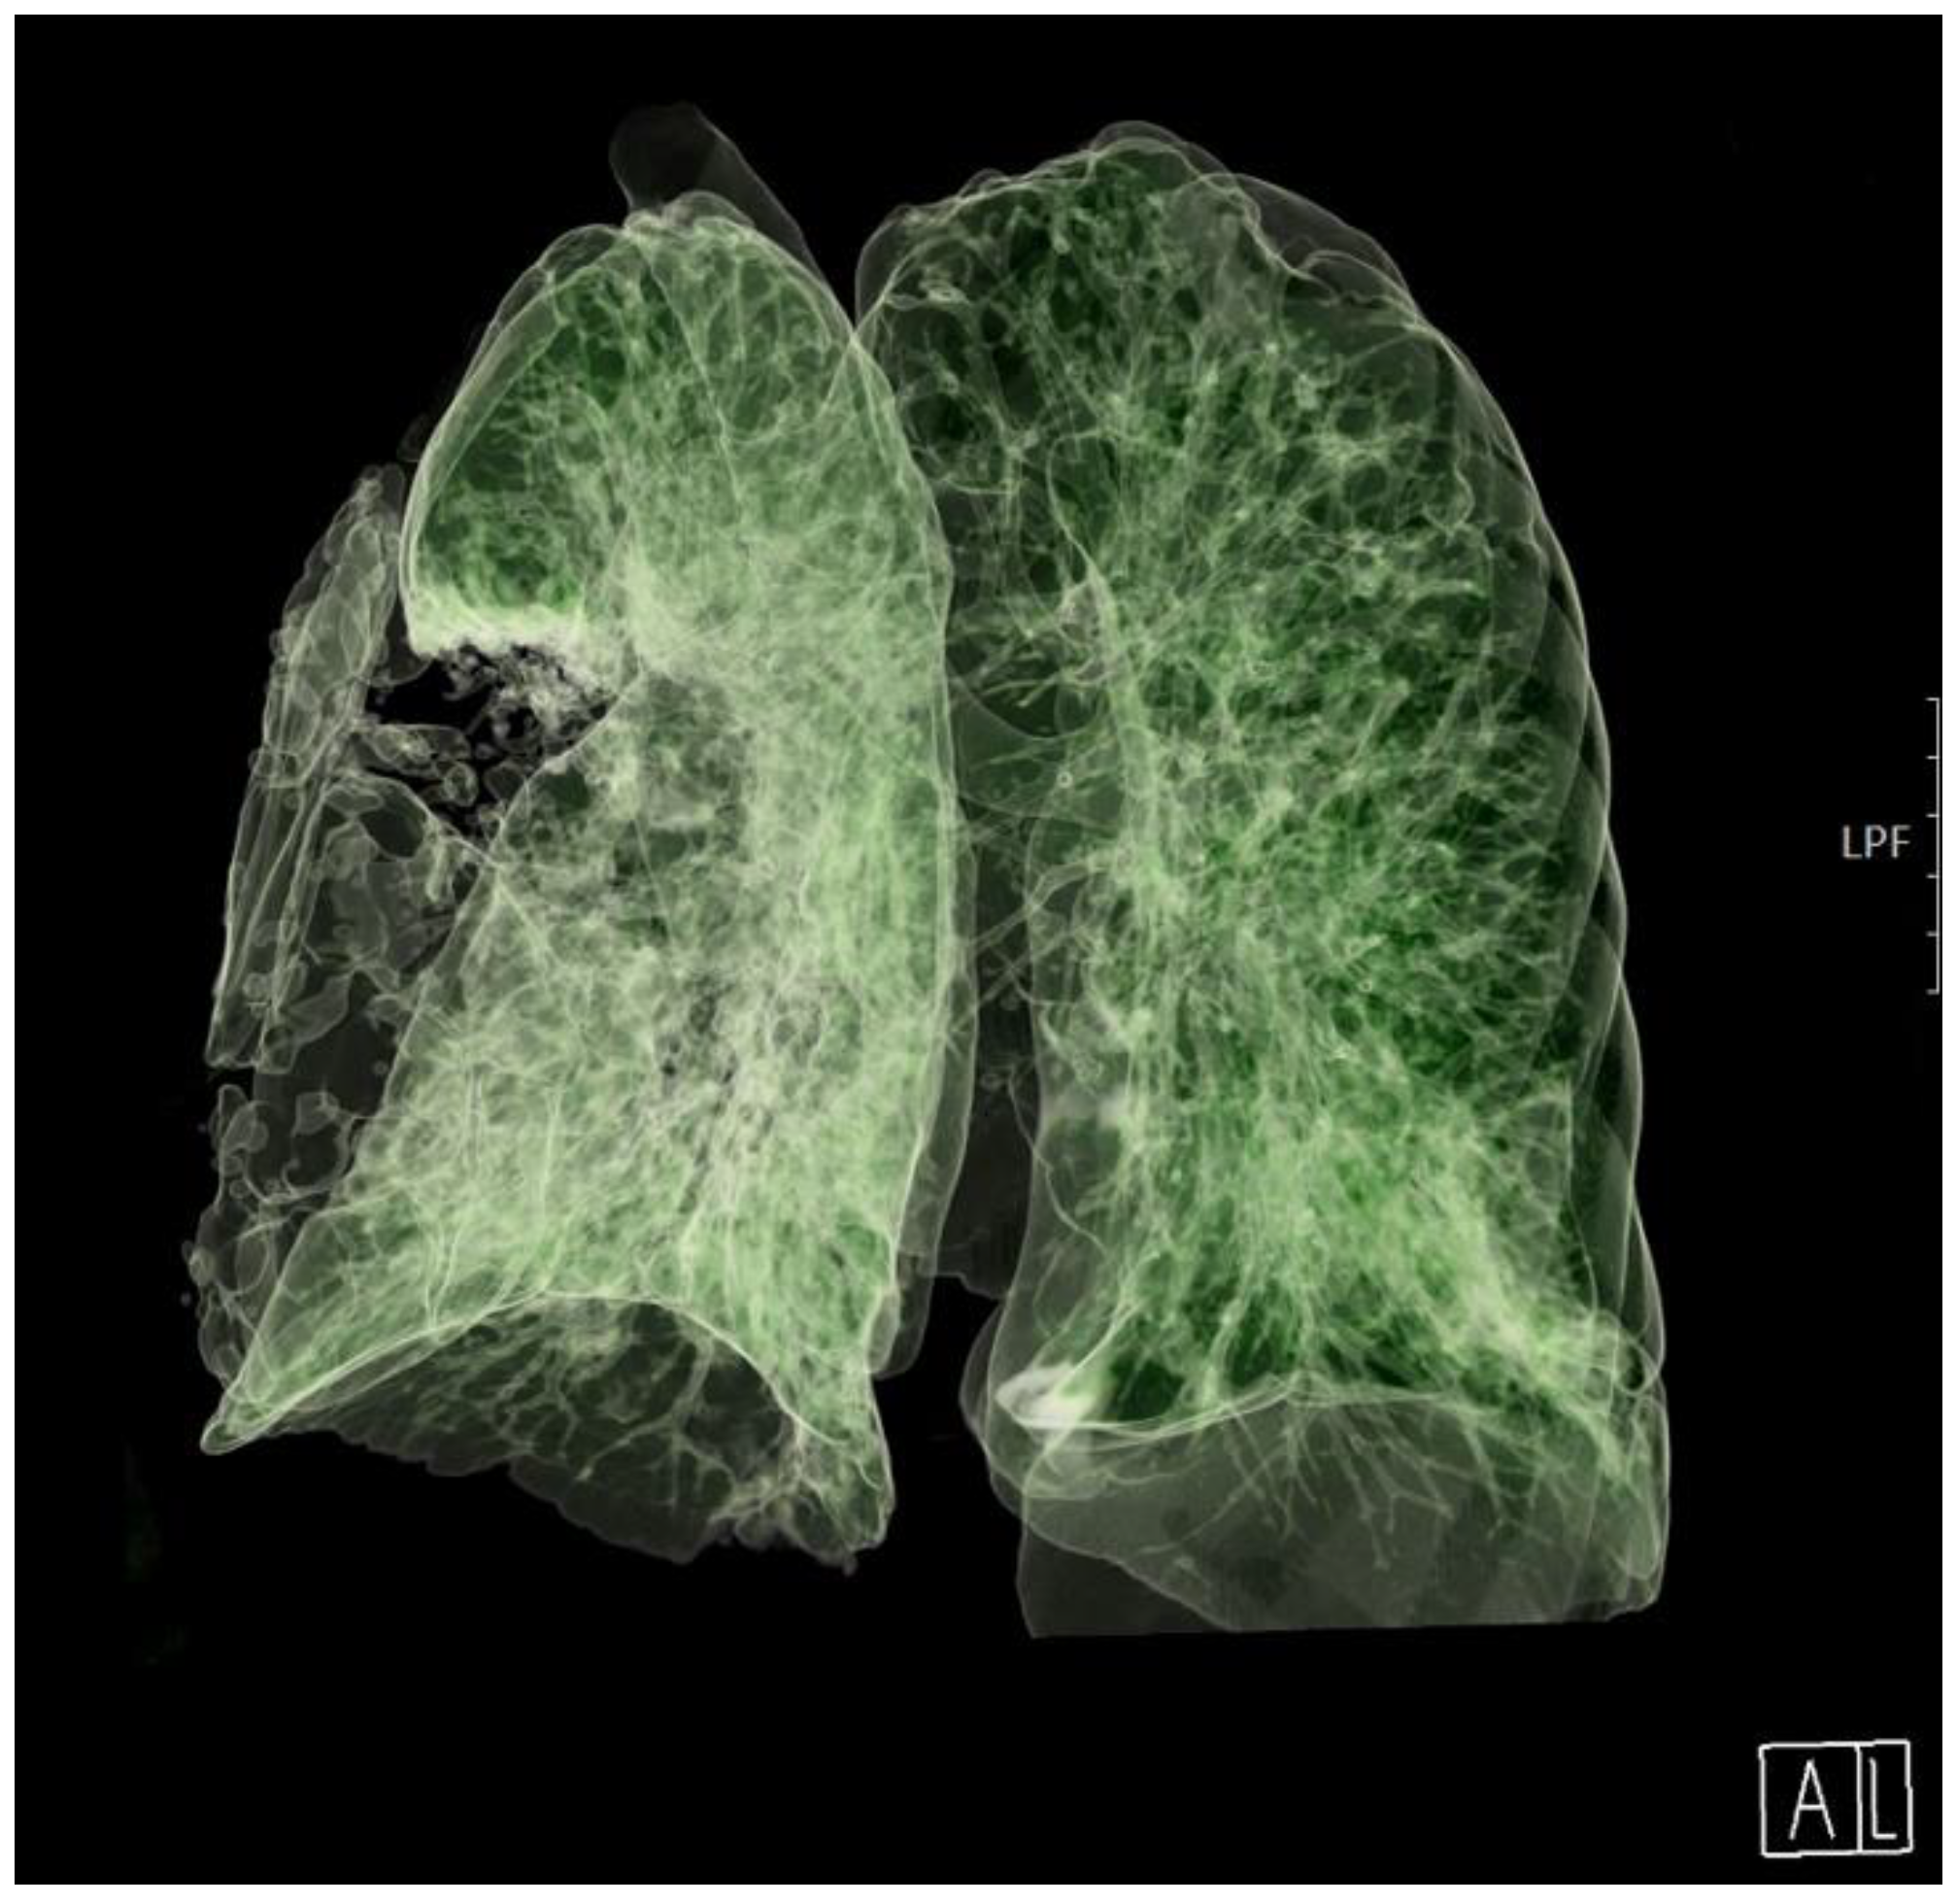

On day 8, due to the patient's restlessness and inability to synchronize with the ventilator, a continuous infusion of dexmedetomidine was introduced, followed by a continuous infusion of midazolam and fentanyl due to extremely difficult ventilation with high oxygen concentrations and respiratory pressures (Paw greater than 30). A control CT of the thorax was performed, which revealed deterioration in terms of the progression of the inflammatory infiltrate to the right lung lobe (Figure 2, Video S1). A thoracic surgeon was consulted several times.

Figure 2. A 3D computed tomography scan of the lungs on day 8. Both bronchi for the right lower and medial lobe were completely obstructed.